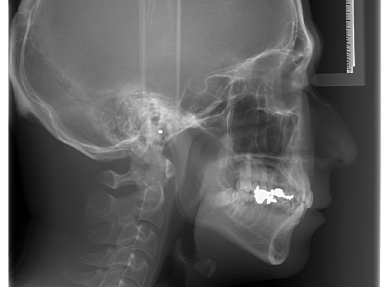

セファログラム(写真上 側貌レントゲン)

横から撮ったレントゲン写真をセファログラムといいますが、これは主に矯正治療に使用して、顎の発育の成長や骨と皮膚との関係を診査するために撮影しますが、骨が高解像度で表示されるのはもとより、皮膚などの軟組織もはっきりと見ることができます。

矯正治療において不正咬合の原因を検討するのがとても大事なのです。歯の位置や傾きなど純粋に歯に問題があるケースか、顎の発育や大きさに問題があるかによって、治療のアプローチや後戻りの程度が大きく異なります。ですから治療を始める前、治療途中でもこれを確認しなががら経過をみることが必要になります。この時セファログラムはとても強い武器になります。